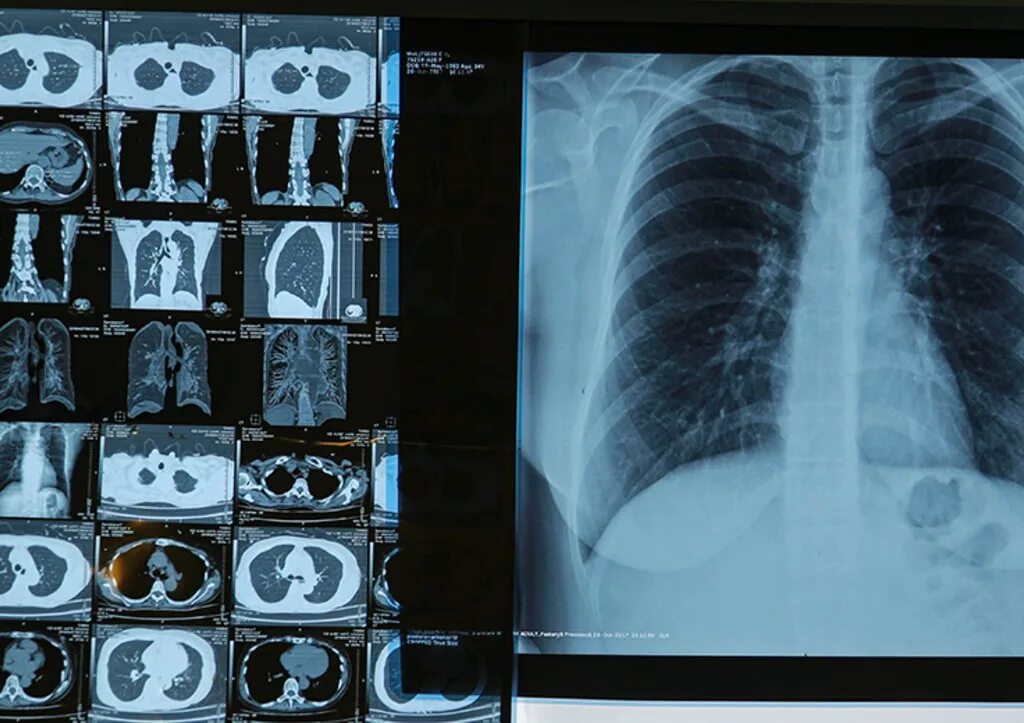

Флюорография видно ли курящего электронную сигарету